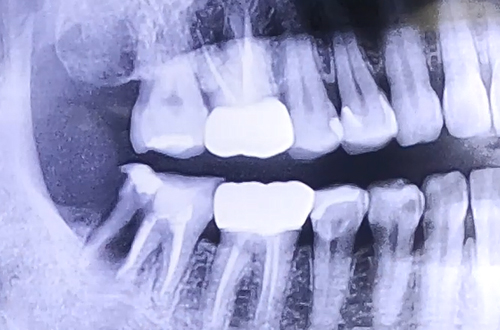

BEFORE

치아에 엄청난 통증을 호소하며 급하게 내원해주신 환자분이십니다.

살펴보니 이미 오래 전에 치료가 다 되었다고 생각했던 충치 치료를 했던 치아가 크게 쪼개진 상태였는데요.